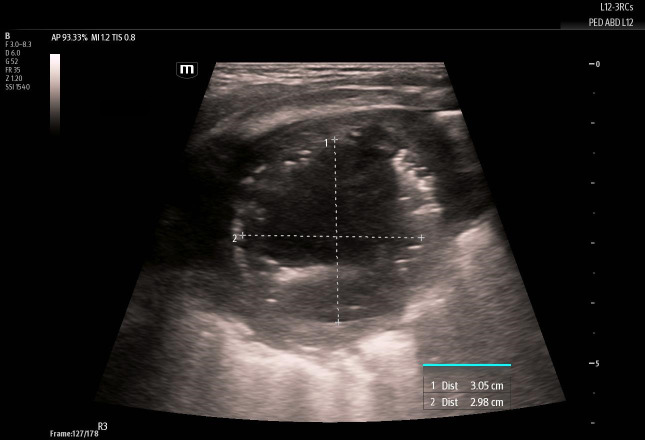

Application of ultrasound to evaluate pediatric respiratory disease in the emergency department setting is rapidly growing, particularly as we often weigh the risks of exposure to radiation with other readily available imaging modalities in the acute care setting. In this case report, we describe how point of care ultrasound (POCUS) was utilized by emergency providers to characterize a lung abscess diagnosed in a pediatric patient. We also compare the ultrasound findings to other imaging studies.

Abstract Image